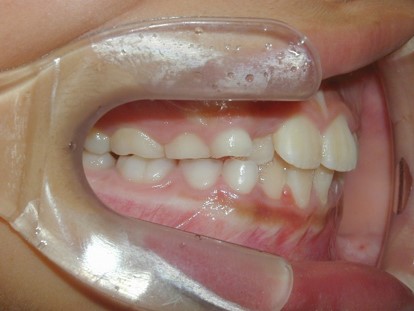

永久歯に交換するためのスペース不足による前歯のガタガタで、取り外しができる拡大床にて上下顎の幅を拡大した後、上顎の前歯をマルチブラケット装置で並べました。治療の期間は1年9か月でした。

初診時

終了時